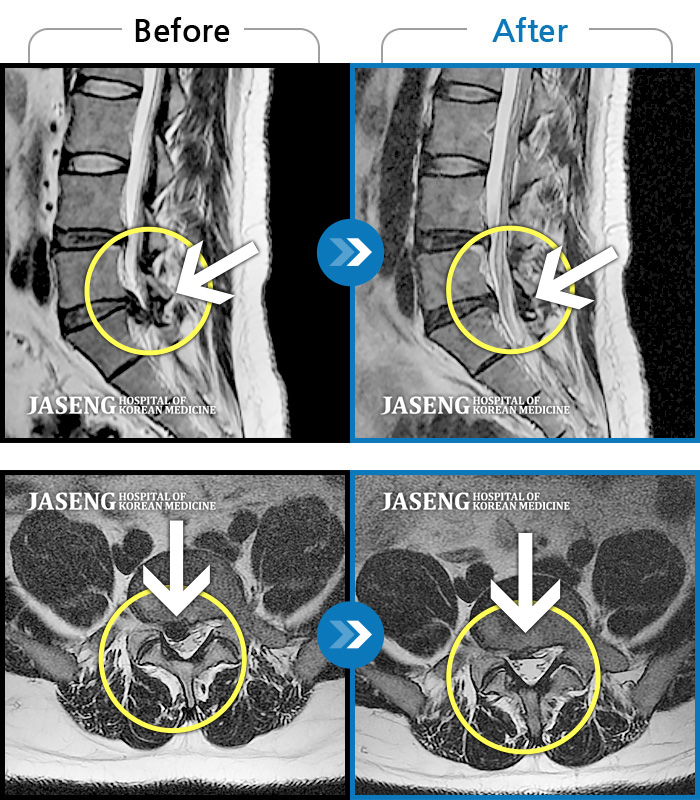

허리디스크

부천 · 신동재 원장

의자 위를 여러 번 올라갔다 내려갔다 반복한 뒤 극심한 하요부 통증 및 좌측 하지부 저림

촬영시기

2024.06.22 ~ 2024.11.19

2024.11.29